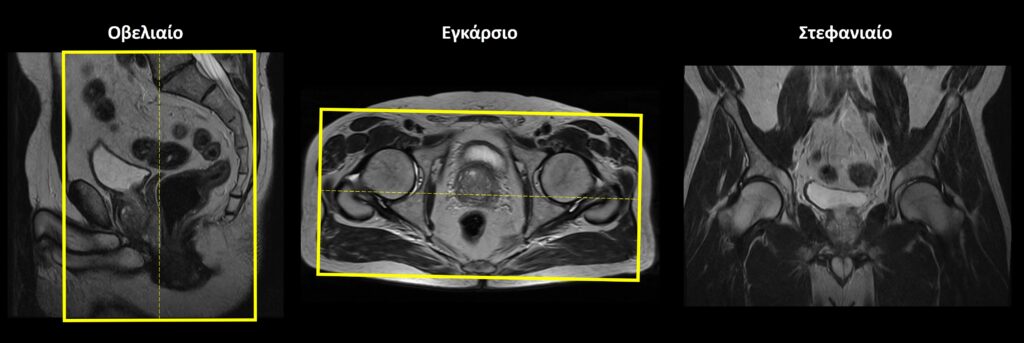

Σχεδιασμός τομών Στατικές Ακολουθίες

Οβελιαίο επίπεδο (Sagittal): οι οβελιαίες τομές σχεδιάζονται κατά μήκος των οργάνων της πυέλου τόσο στο εγκάρσιο όσο και στο στεφανιαίο επίπεδο. Η κλίση των τομών στο εγκάρσιο επίπεδο πρέπει να είναι παράλληλη με τη νοητή γραμμή που ενώνει την ηβική σύμφυση με τον πρωκτικό σωλήνα. Κατάλληλη κλίση πρέπει να δοθεί και στο στεφανιαίο επίπεδο, παράλληλα με το ορθό και τον πρωκτικό σωλήνα. Οι τομές πρέπει να περιλαμβάνουν τα όργανα της πυέλου, από την δεξιά έως την αριστερή κοτύλη.

Εγκάρσιο (Axial/Transversal): οι εγκάρσιες τομές σχεδιάζονται παράλληλα με τις κεφαλές των μηριαίων στο στεφανιαίο επίπεδο και κάθετα στονπρωκτικό σωλήνα στο οβελιαίο επίπεδο. Οι τομές πρέπει να περιλαμβάνουν τα όργανα της πυέλου, από τις λαγόνιες ακρολοφίες (πάνω) έως τον πρωκτό (κάτω).